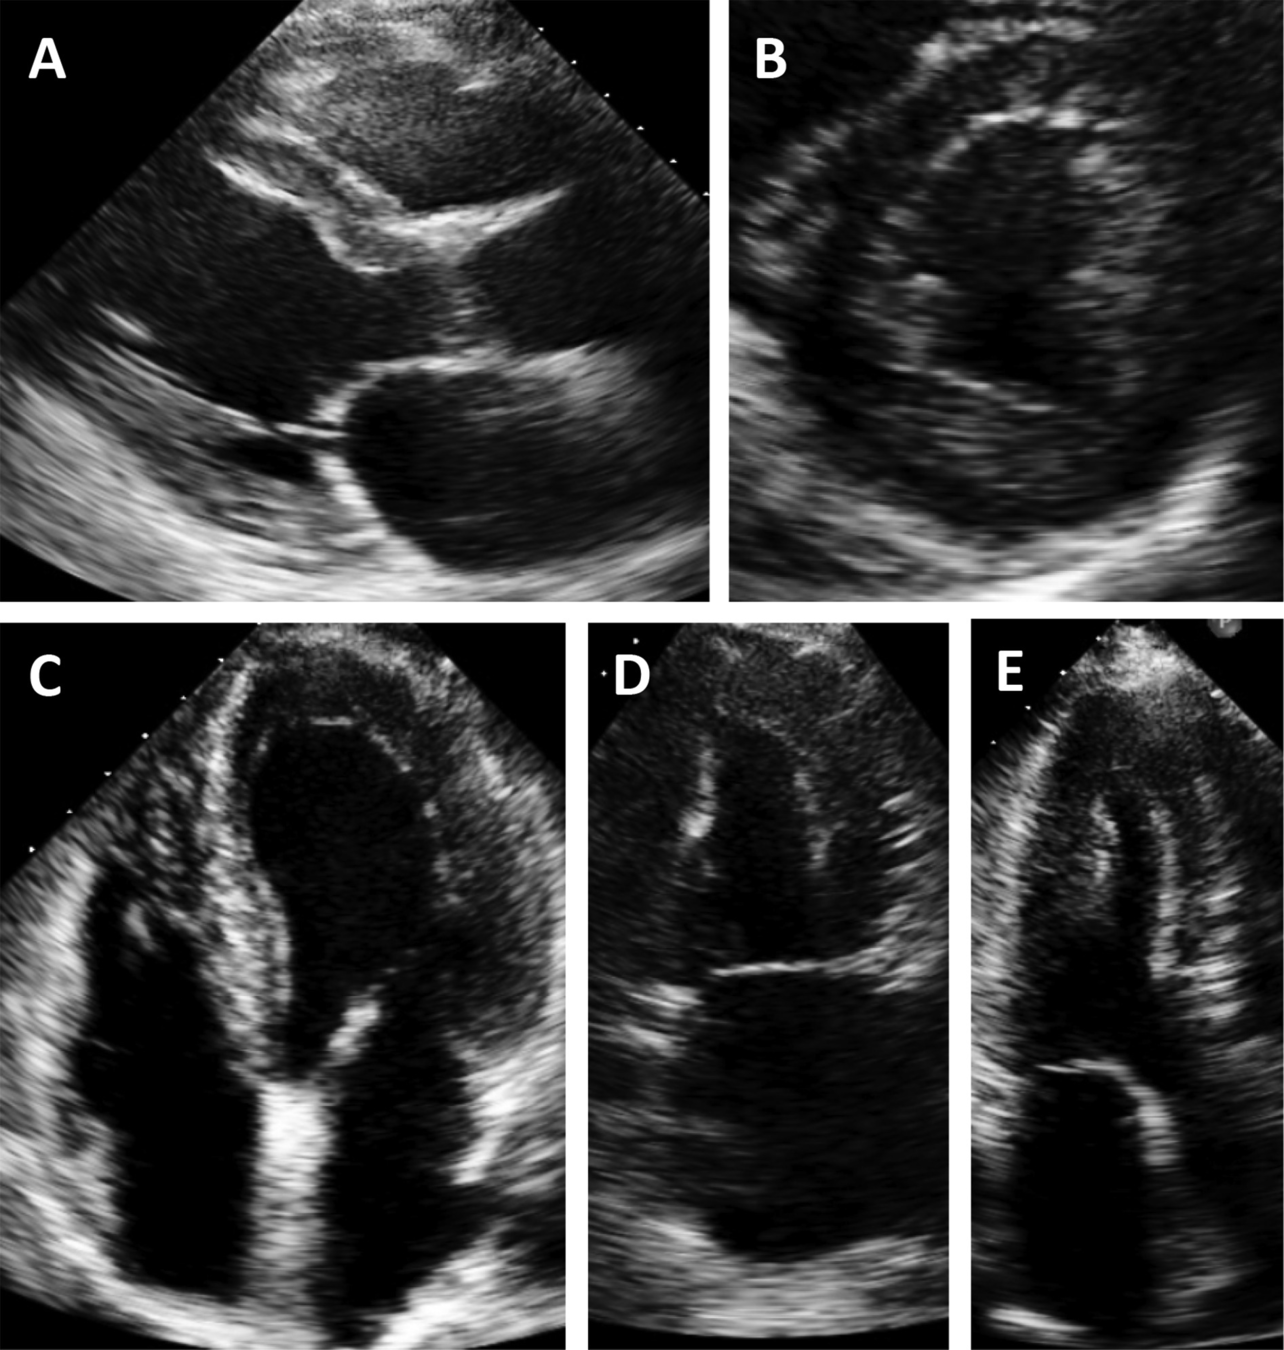

LV Bands

False Tendon

Muscular Band

Papillary Muscle

• Found in over 50% of LV in autopsy studies

• Unlike trabeculations, they traverse the LV cavity

• Echo free space on both sides

• Taut in diastole, laxe in systole

• Can have broad base attachment

• Can rupture in MI or spont